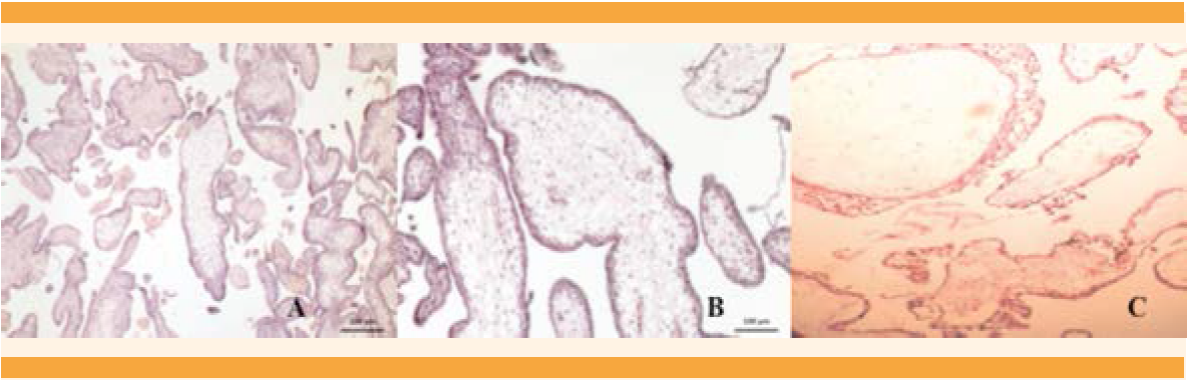

Figura 3 Imágenes microscópicas. Vellosidades del tercer trimestre del embarazo. Se distinguen dos tipos de vellosidades: A y B. En el centro se observan troncos vellosos, con grandes vasos, sin alteraciones, rodeados de vellosidades coriales correspondientes al tercer trimestre de la gestación, sin hiperplasia del trofoblasto. C. Vellosidades molares, con edema vesicular y aumento de tamaño; ausencia de vasos sanguíneos e hiperplasia del trofoblasto, sin atipias. No se mezclan con las primeras.

Desde la perspectiva microscópica se observaron dos tipos de vellosidades. En una placenta las vellosidades eran del tercer trimestre, en límites normales; otras, sin mezclarse con las primeras, fueron hidrópicas, avasculares y con grados variables de hiperplasia del trofoblasto (Figura 3). Con estos tres elementos se integró el diagnóstico histológico de mola completa. Este caso se suma a los 78 reportados de mola hidatiforme completa y nacimiento de feto vivo sano, que supervive.21

El caso 2 correspondió a mola parcial o incompleta con feto vivo (Figura 4), que cursó clínicamente de manera atípica. La bibliografía reporta que rara vez se asocia con complicaciones médicas y casi siempre la hCG es menor de 100,000 mUI/mL.22 En este caso se asoció con hiperemesis, hipertiroidismo, preeclampsia severa, placenta previa y β-hCG de 482,174 mUI/mL. Además, el feto no tuvo malformaciones congénitas mayores, aunque no se confirmó o descartó triploidia porque no fue posible obtener el cariotipo. Lembet y sus colaboradores23 reportaron un caso semejante con feto vivo de 560 g, que no sobrevivió a los cuidados neonatales intensivos, el cariotipo del feto y la placenta fue 46XY. Está reportado que 32% de los casos de mola parcial pueden tener cariotipos normales.24 En el caso aquí comunicado el diagnóstico temprano de mola incompleta se derivó del estudio temprano del ultrasonido pélvico-abdominal del primer trimestre del embarazo, que mostró imágenes focalizadas de “placenta quística”, sugerentes de mola hidatiforme parcial, además de concentraciones séricas de hCG mayores de 100,000 mUI/mL. El estudio histopatológico confirmó dos tipos de vellosidades (Figura 5). Desde el punto de vista histológico y biológico todo lo anterior cumplió los criterios de mola parcial, que es la mezcla en la misma placenta de vellosidades normales y vellosidades hidrópicas, pero sin hiperplasia del trofoblasto (Figura 6). Estos hallazgos deberían complementarse con una biopsia de las vellosidades coriales o una amniocentesis, para evaluar el cariotipo y normar la decisión clínica.